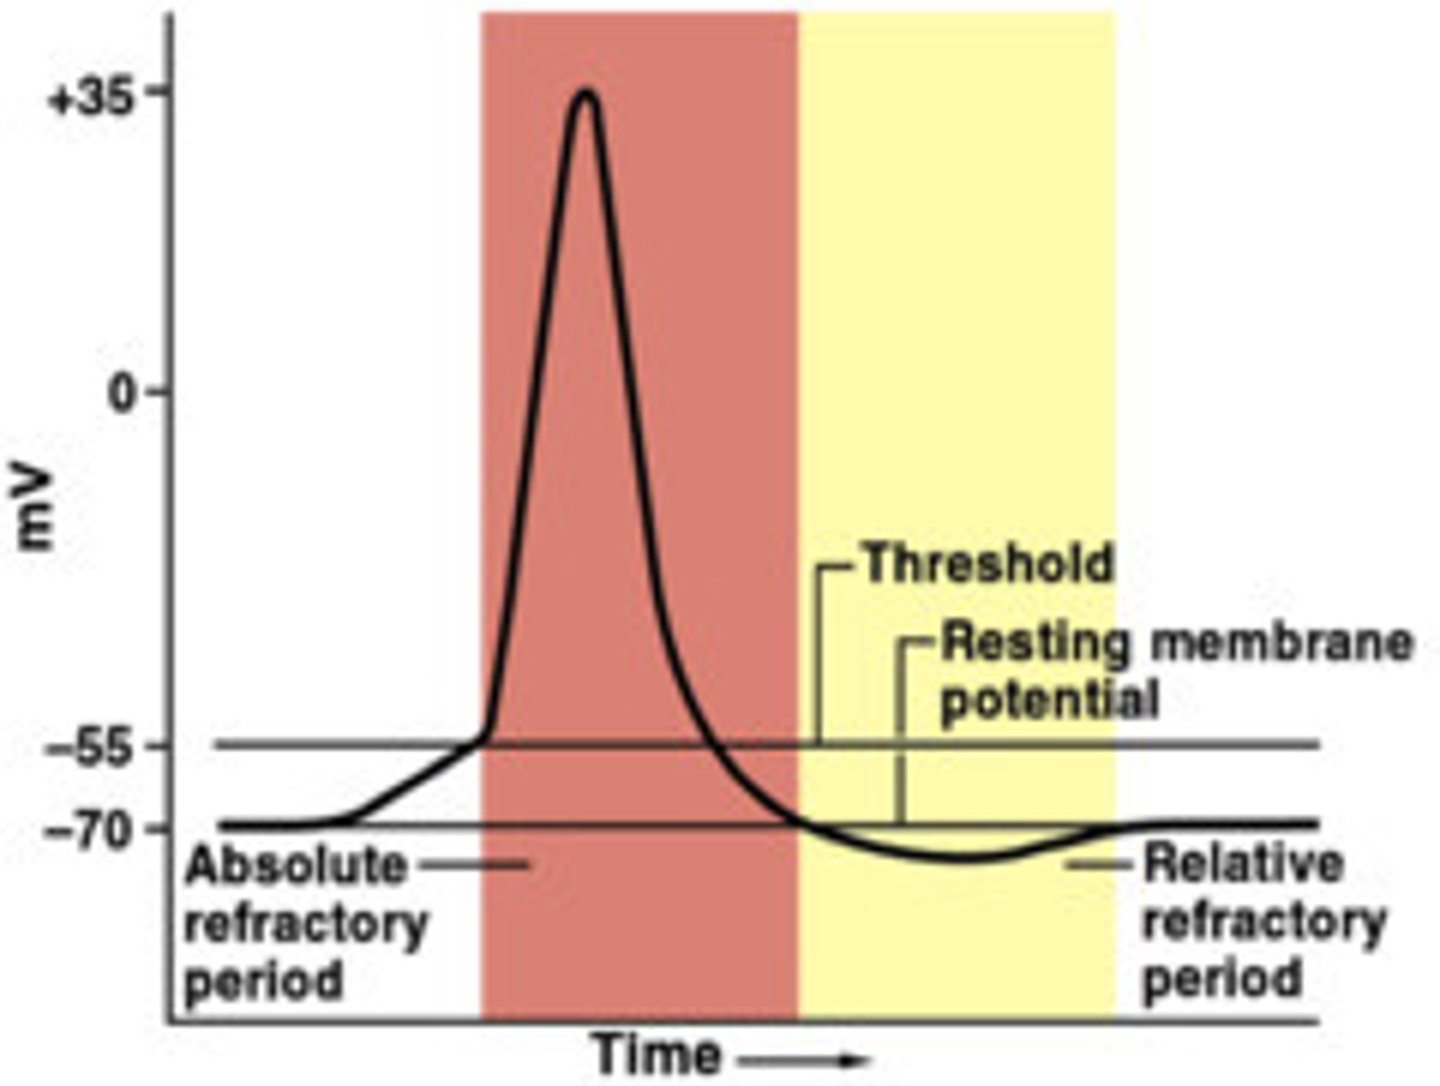

Threshold

the membrane voltage that must be reached in an excitable cell (e.g., neuron or muscle cell) in order to generate an action potential

Refractory period

after a neuron has fired; the time following an action potential during which a new action potential cannot be initiated

Resting potential

the state of the neuron when not firing a neural impulse